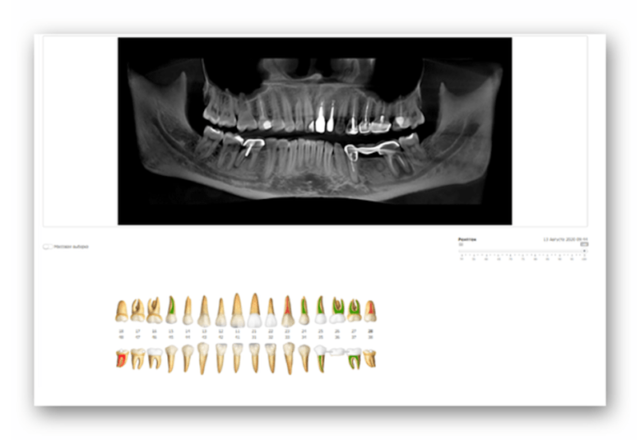

Диагностика

Перед лечением зубов нужно провести полное обследование полости рта. Для этих целей назначается компьютерная томография или ортопантомограмма.

На основе рентгеновских снимков и визуального осмотра определяются:

- безнадежно разрушенные зубные единицы — их придется удалить;

- условно сохраняемые — можно попытаться вылечить, но при отрицательном результате их вырывают;

- зубы, нуждающиеся в лечении — их однозначно получится сохранить;

- здоровые зубные единицы — в лечении не нуждаются.